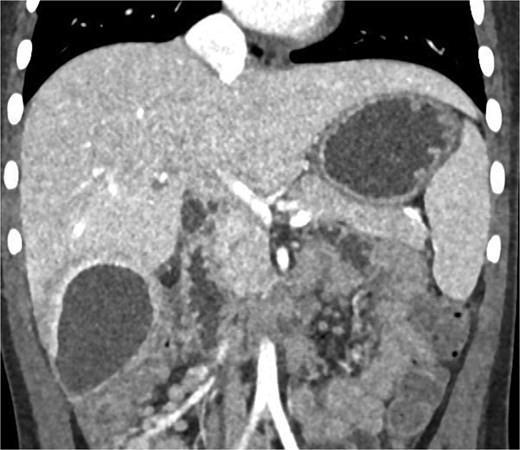

Imaging plays a crucial role in diagnosing appendicitis and its complications. Ultrasound is often the initial modality used, but it may have limited sensitivity in detecting intra-abdominal abscesses, particularly when the appendix is not visualized or when findings are inconclusive [4, 5]. In such cases, contrast-enhanced CT is considered the gold standard, providing detailed visualization of the appendix and associated complications, including abscess formation [2, 4]. In the present case, the initial ultrasound findings suggested an atypical position of the appendix and a pathological fluid collection, but CT imaging confirmed a retrocecal appendix and subhepatic abscesses (Figs 4 and 5), guiding appropriate management.

CT axial view of a subhepatic abscess. Contrast-enhanced capsule and fluid-air level visible.